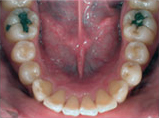

齒列擁擠的不正咬合經由擴大效果排列整齊:

Before

Proceeding

After